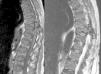

RMN dorsolumbar: la RMN con corte sagital en T1 y T2 de columna dorsolumbar, que presenta una lesión focal en los elementos posteriores izquierdos del cuerpo vertebral D10 que implica al pedículo, pars y lámina, con carácter expansivo, rodeado por una fina cáscara de hueso perióstico neoformado, que mide 3,7cm de diámetro máximo, presentando componentes de partes blandas e invadiendo el canal raquídeo, donde provoca una clara compresión medular con adelgazamiento de la misma. Se manifiesta con señal intermedia en todas las secuencias de pulso y creemos compatible con un tumor pardo (osteoclastoma)1,2.